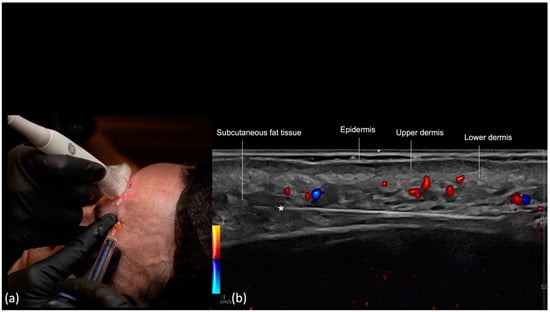

- Scan before injecting: The treatment area is scanned immediately before injection to assess the presence of vessels. The trajectory of the main arteries might be marked on the patient’s skin.

- Scan while injecting: In this case, the cannula is visualized in real time and positioned in the desired anatomical region, avoiding vascular structures.